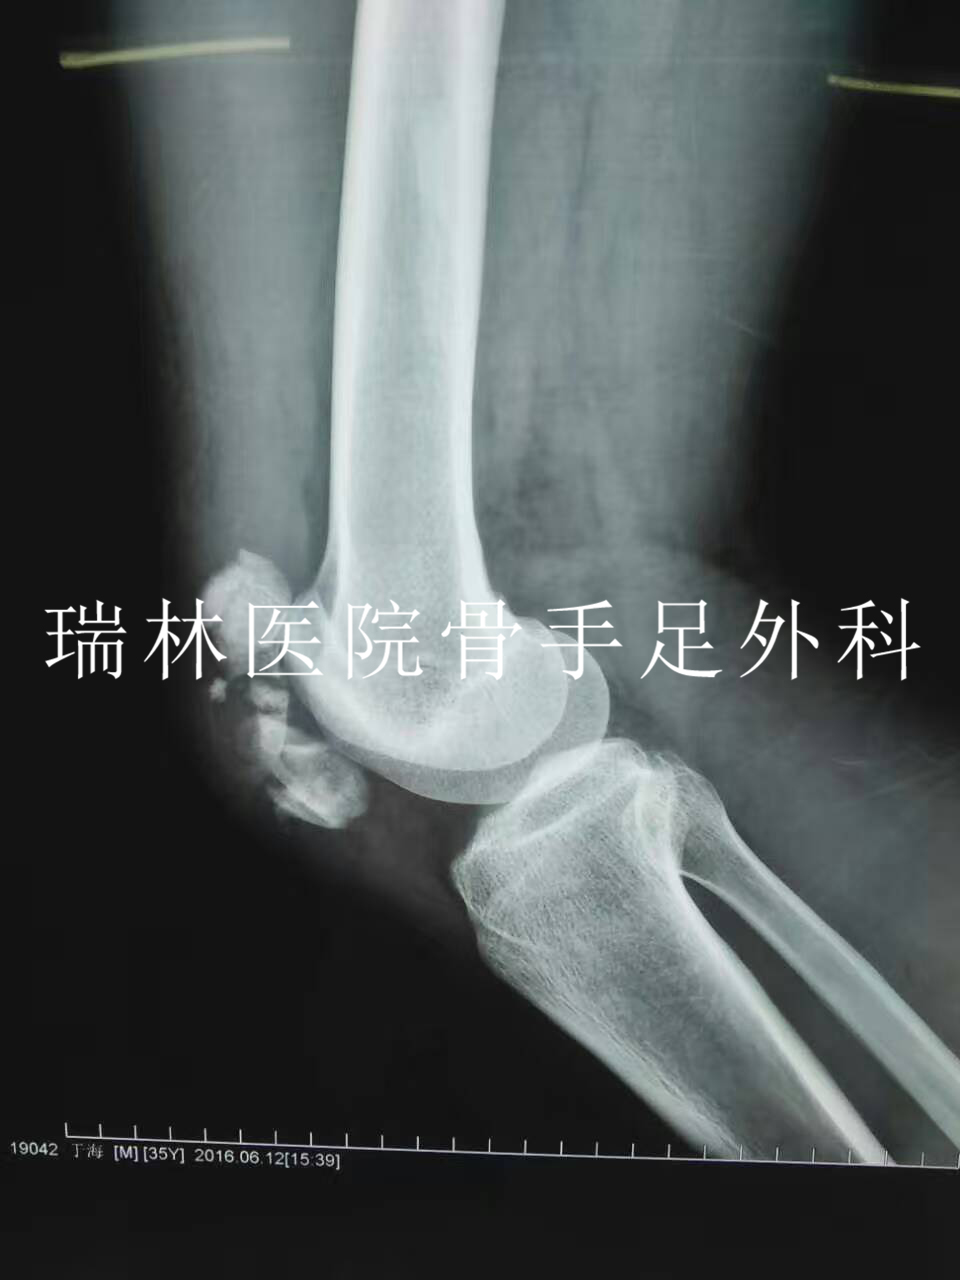

李XX断肢再植手术